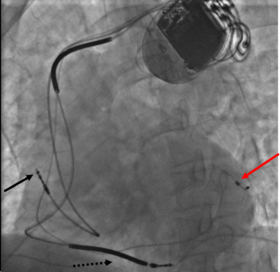

Cardiac resynchronization therapy (CRT) is used for people with heart failure in whom the left and right ventricles do not contract simultaneously (ventricular dyssynchrony), which occurs in approximately 25–50% of heart failure patients. To achieve CRT, a biventricular pacemaker (BVP) is used, which can pace both the septal and lateral walls of the left ventricle. By pacing both sides of the left ventricle, the pacemaker can resynchronize the ventricular contractions.

CRT devices have at least two leads, one passing through the vena cava and the right atrium into the right ventricle to stimulate the septum, and another passing through the vena cava and the right atrium and inserted through the coronary sinus to pace the epicardial wall of the left ventricle. Often, for patients in normal sinus rhythm, there is also a lead in the right atrium to facilitate synchrony with the atrial contraction. Thus, timing between the atrial and ventricular contractions, as well as between the septal and lateral walls of the left ventricle can be adjusted to achieve optimal cardiac function.

CRT devices have been shown to reduce mortality and improve quality of life in patients with heart failure symptoms; a LV ejection fraction less than or equal to 35% and QRS duration on EKG of 120 ms or greater.[37][38]

Biventricular pacing alone is referred to as CRT-P (for pacing). For selected patients at risk of arrhythmias, CRT can be combined with an implantable cardioverter-defibrillator (ICD): such devices, known as CRT-D (for defibrillation), also provide effective protection against life-threatening arrhythmias.[39]